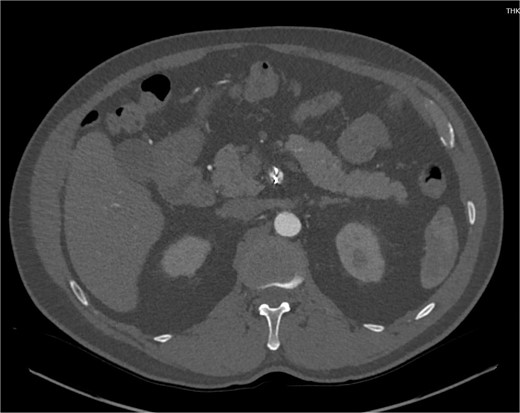

A 60-year-old male with a past medical history of hypertension presented to our emergency department with 45 minutes of severe abdominal pain accompanied by nausea and vomiting. The patient’s presenting blood pressure was 192/130 mmHg with a heart rate of 77 bpm, and the remaining vitals were within normal limits. On physical examination, tenderness was noted in the epigastric region without peritoneal signs. A CT of the abdomen and pelvis revealed a partial thrombosis of the SMA, extending into some of the mesenteric branch arteries, with no evidence of bowel ischemia. The patient was started on a high-dose heparin drip. A same-day repeat CT angiogram further indicated 75% SMA stenosis secondary to SMA dissection with thrombosis of the false lumen (Fig. 1).

CTA abdomen and pelvis demonstrating 75% SMA stenosis secondary to SMA dissection with thrombosis of the false lumen.